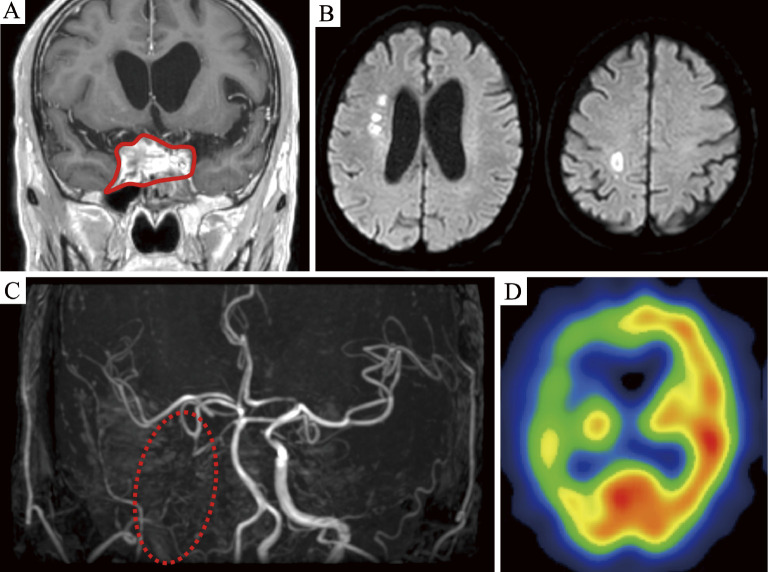

We report a case of invasive sphenoid sinus aspergillosis with progressive internal carotid artery (ICA) stenosis and contralateral carotid occlusion that was successfully treated with percutaneous transluminal angioplasty and stenting (PTAS). A 70-year-old man presented with right-sided visual disturbance, ptosis, and left hemiparesis. Magnetic resonance imaging of the head revealed a space-occupying lesion within the sphenoid sinus with infiltration of the bilateral cavernous sinuses, right ICA occlusion, and multiple watershed cerebral infarcts involving the right cerebral hemisphere. The patient was diagnosed with invasive sinus aspergillosis based on transnasal biopsy findings. Despite intensive antifungal therapy using voriconazole, rapidly progressive aspergillosis led to a new stenotic lesion in the left ICA, which increased the risk of bilateral cerebral hypoperfusion. We performed successful PTAS to prevent critical ischemic events. Finally, aspergillosis was controlled with voriconazole treatment, and the patient was discharged. He showed a favorable outcome, with a patent left ICA observed at a 3-year follow-up. PTAS may be feasible in patients with ICA stenosis and invasive sinus aspergillosis.